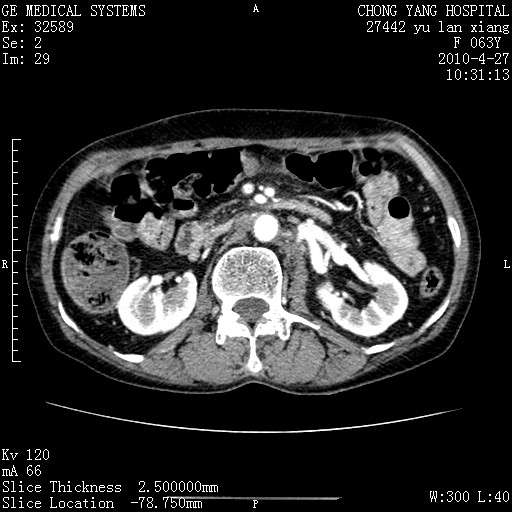

标题: CT26066:F63Y 上腹正中压痛半月,CA199:7400u/ml,MR示胰腺炎伴 [打印本页]

标题: CT26066:F63Y 上腹正中压痛半月,CA199:7400u/ml,MR示胰腺炎伴

胰腺癌侵犯腹腔动脉干-分支、胃壁、左侧膈肌伴胰周及腹膜后淋巴结转移、胆囊切除术后。

胰腺癌侵犯腹腔动脉干-分支、胃壁、左侧膈肌伴胰周及腹膜后淋巴结转移、胆囊未显影。